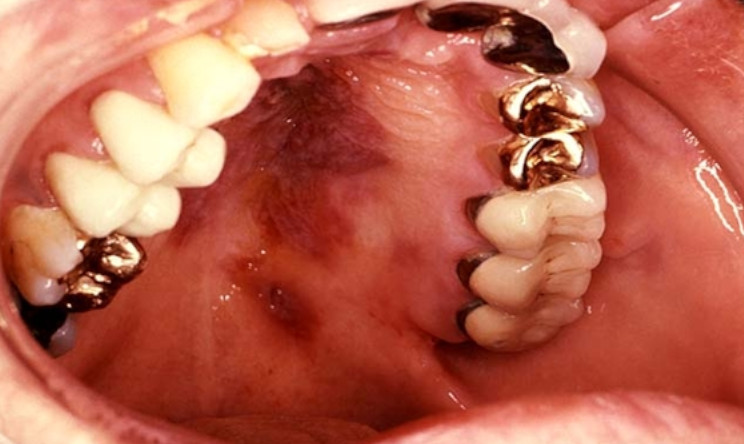

É a doença mais importante associada ao HHV-8, sendo uma desordem multifocal proliferativa de origem vascular, encontrada em quatro formas epidemiológicas mais frequentes: 1) associada à AIDS (AIDS-SK), mais observada em homens homo/bissexuais HIV-1 positivos; 2) o SK Africano (SKA), mais prevalente em certos locais da África e que corresponde a 10% dos tumores encontrados nestes locais, podendo adquirir uma forma muito agressiva após infecção por HIV-1; 3) o SK clássico (SKC) que ocorre em pacientes idosos de certas áreas do oeste do Mediterrâneo, com característica mais branda; e 4) SK associado à terapia imunossupressora pós-transplantes, denominada SK pós-transplante (PKS). A lesão é caracterizada por múltiplas manchas, de aparência nodular ou planar, principalmente nas extremidades do corpo, envolvendo mucosa e vísceras, principalmente na AIDS-SK. O estágio final é representado por uma fase tumoral nodular.